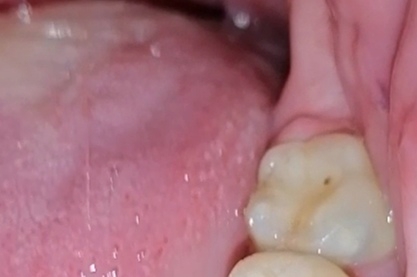

Аноним 05/03/26 Чтв 20:46:51 1661060 244

1111.jpg 33Кб, 214x627

214x627

Сапдвач а кто-то из шарящих на доске есть?

Нужна будет имплантация переднего верхнего + постановка 2х коронок по обе стороны импланта. С одной стороны зуб перелечивали, восстановили коронковую часть и терапевт сказала моя работа здесь закончена.

Второй зуб пикрил спереди и с обратной стороны как выглядит. Был восстановлен лет 8 назад пломбой + вкладкой, половина зуба (меньшая его часть слева на фотке спереди) родная остальное пломба, спереди как видно кариес под ней нарисовался + с обратной стороны пиздец нагромождение массы даже не уверен что там родное а что пломба + приклеен к соседнему кривому. Терапевт сказала что пролеченные корни на КТ с виду норм у него.

Вопрос: при установке коронок ортопед обтачивает зубы или мне нужно опять к терапевту привести в человеческий вид оба зуба с фотки до ортопеда и терапевтом же их обточить?

И вопрос по имплантации, насколько критично делать в одной и той же клинике имплант + обе коронки? Передние зубы как никак, эстетика очень важна. Медентика норм имплант или лучше на астра тек\штрумана раскошелиться? И какие подводные в формировании стоимости коронок? Внятного ценника не могу найти, везде "От", в лучше случае указано порядка 30-35 за циркониевые\е-максы но непонятно то там сверху по доп работам встанет.